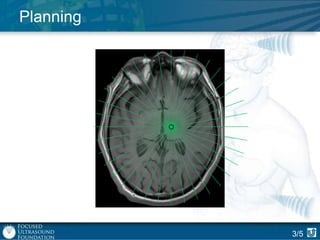

Planning

3/5

Procedure: Planning

Automatic planning